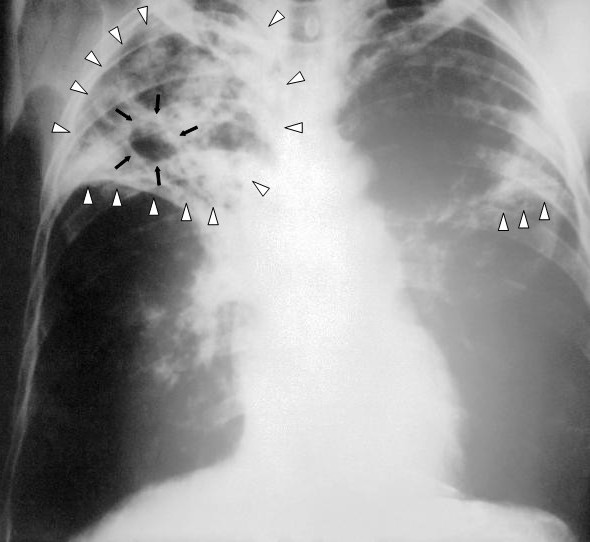

Gruźlica to problem globalny; wciąż prowadzone są badania nad ulepszeniem szczepionki na tę chorobę zakaźną – mówi PAP prof. Camille Locht, który współuczestniczy w tworzeniu nowej generacji szczepionek przeciwko gruźlicy. Jej leczenie tylko w Europie pochłania rocznie 5 mld euro.

Fot. Wikipedia